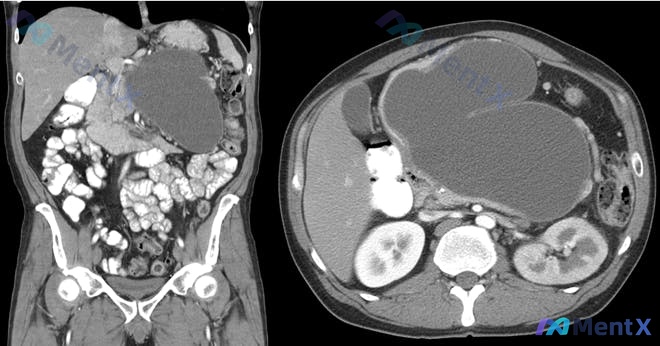

整理了一份病例讨论材料,最终诊断已经明确。先不放结论,只看前期资料,大家会觉得肿块里是什么? 病例摘要: - 患者:44 岁男性 - 主诉:持续腹部饱胀感、血尿 - 既往史:慢性腹痛,每日饮酒约 6 杯啤酒,有大麻史(目前否认) - 体征:腹部大而触痛肿块,生命体征平稳 - 实验室:血清肌酐升高 -...